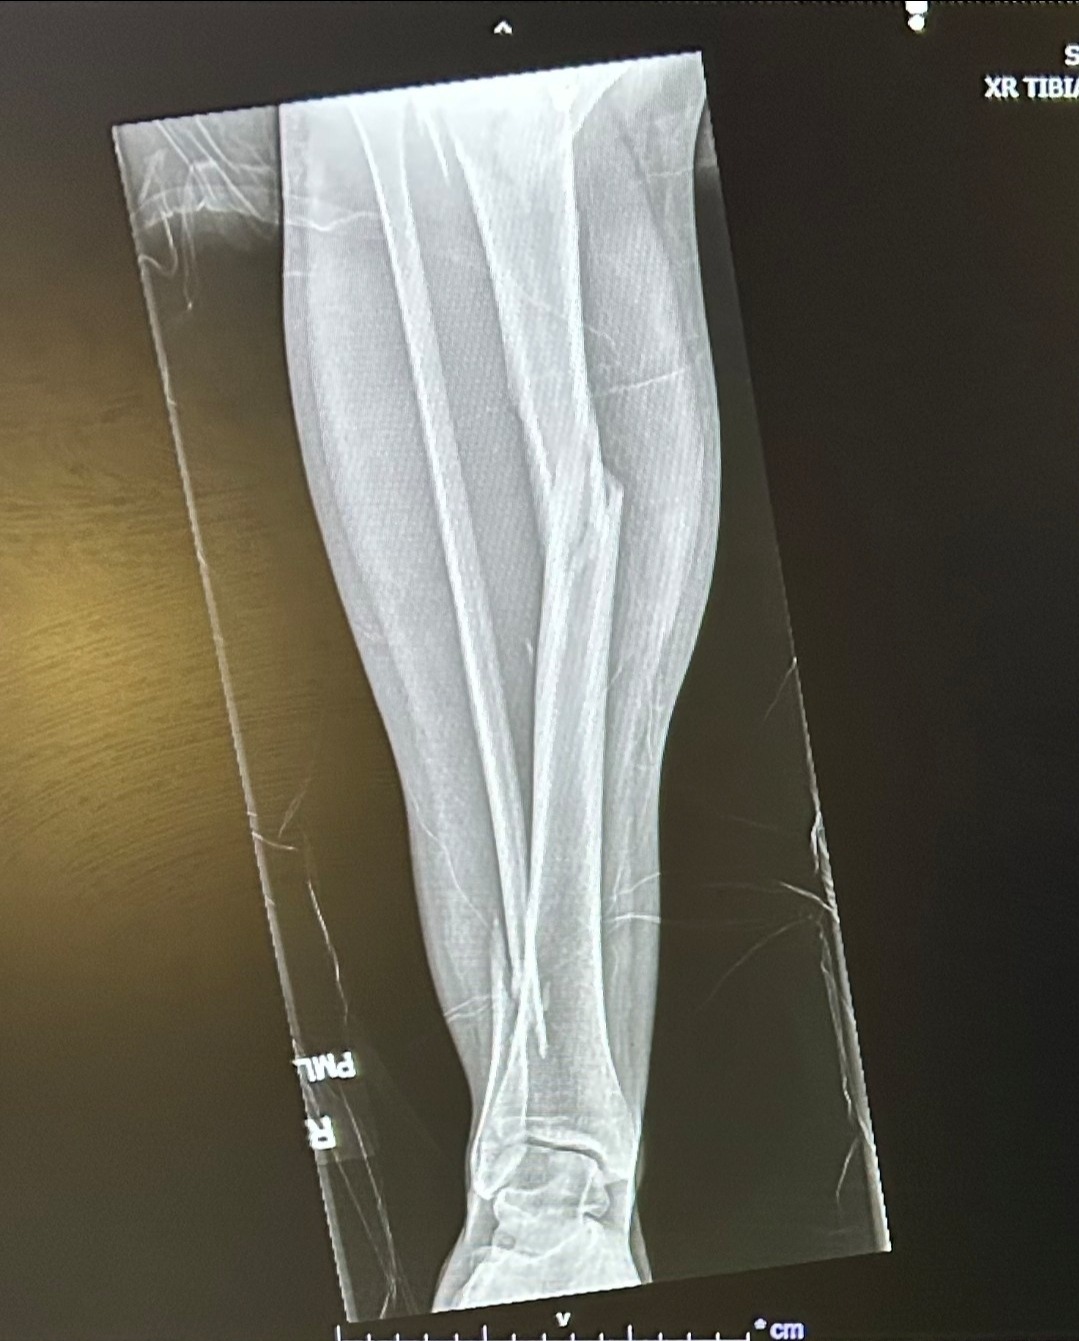

Earlier this year, Robin suffered a severe leg injury in a ski accident when she hit a rock hidden beneath the snow. The accident required multiple surgeries and a long, difficult recovery process. On top of that, she had already endured the heartbreaking loss of her boyfriend in a climbing accident last summer.